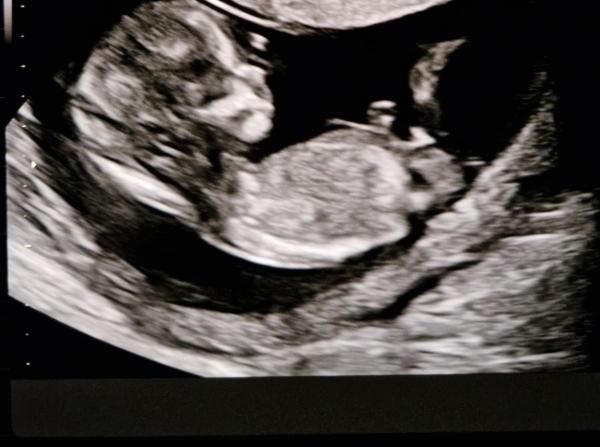

Was bekommt meine Freundin? Junge oder Mädchen?